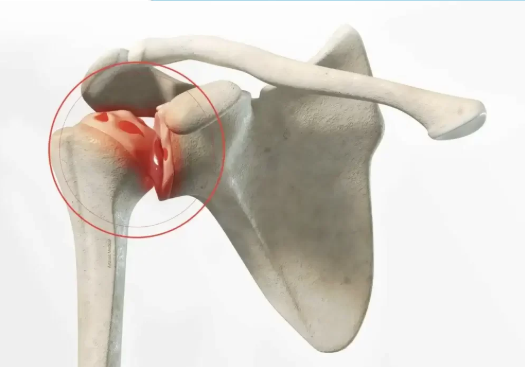

Après un traumatisme, les ligaments peuvent perdre leur fonction stabilisatrice. La chirurgie de l’épaule rétablit la solidité ligamentaire et assure une stabilité durable lors des activités quotidiennes.